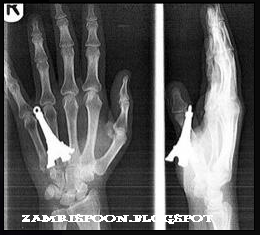

Amy Preston berjoging dan terjatuh menyebabkan

keychainnya yang berbentuk Eiffel Tower tembus kat tangannya